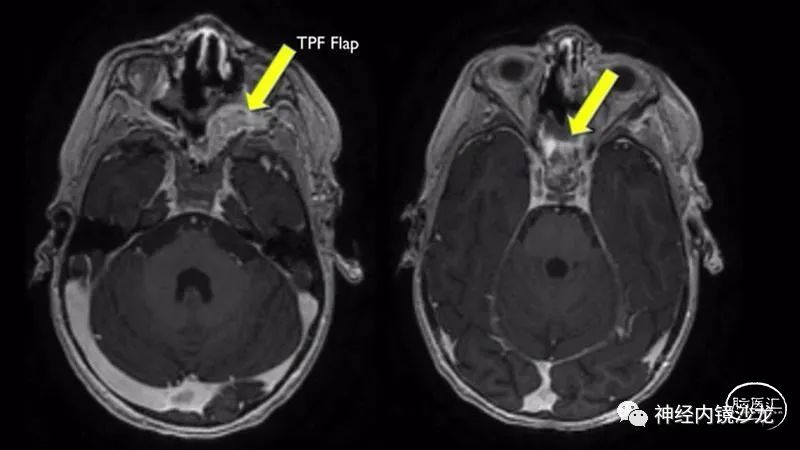

术后第9天,患者出现因为鼻中隔皮瓣坏死导致的神经功能减退和脑内积气。尝试了两次用鼻腔侧壁粘膜瓣进行鼻内修复均未成功。然后采用颞顶筋膜瓣并将其从颞部转移至翼颚窝,并成功修复颅底缺损。患而恢复良好,无神经功能异常。